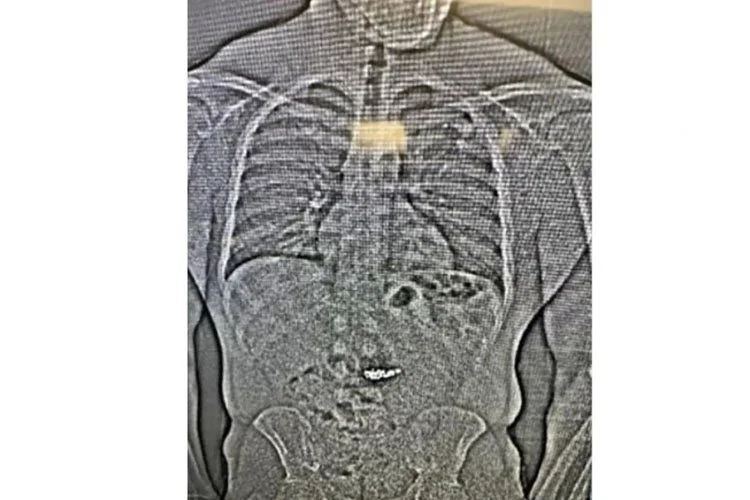

Phim X-quang cho thấy vật thể lạ trong hệ tiêu hóa của Gilder. Ảnh: AP

Ảnh chụp X-quang cho thấy có vật thể lạ trong đường tiêu hóa của Gilder và giới chức nghi ngờ đây là các bông tai kim cương trị giá 770.000 USD bị cướp, nhưng cần chờ cảnh sát hạt Washington xác nhận bằng cách thu thập sau khi Gilder thải ra qua đường tiêu hóa.